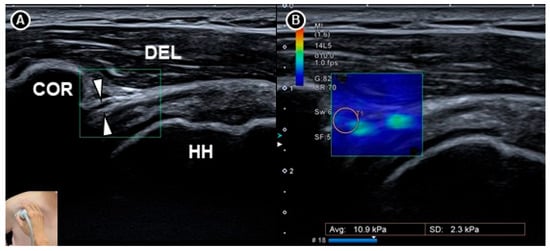

Wu and colleagues [36] examined the elasticity of the coracohumeral ligament using shear wave elastography in 20 patients with clinically suspected adhesive capsulitis and 30 healthy individuals (Figure 7). Measurements of ligament thickness and stiffness were taken from both shoulders in the neutral position and under maximal external rotation. Among the patients, the symptomatic shoulders showed significantly greater coracohumeral ligament thickness (p < 0.001) and a higher elastic modulus in the neutral position (median 234.8 kilopascals, interquartile range 174.4 to 256.7) compared to the asymptomatic side (median 203.3 kilopascals, interquartile range 144.1 to 242.7; p = 0.004). However, this difference was not statistically significant under maximal external rotation (p = 0.123).

Figure 7. Shear wave sonoelastography of the coracohumeral ligament (white arrowheads) shown in grayscale imaging (A) and color elastogram (B). The figure was redrawn by the authors with reference to Wu et al. [36]. DEL, deltoid muscle; COR, coracoid process; HH, humeral head.